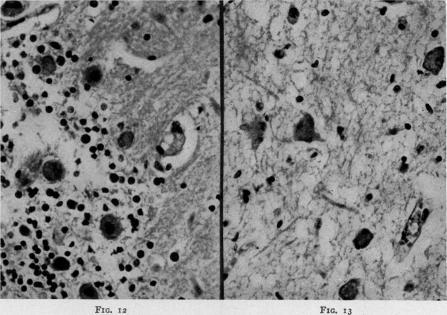

Studies on the Toxemia Syndrome After Burns II: Central Nervous System Changes as a Cause of Death.

Ann Surg. 1945 Mar;121(3):301-13. doi: 10.1097/00000658-194503000-00005.